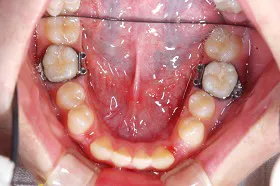

奥歯を1本長期間失ったケース

■治療前

向かって左の下の奥歯が、長期間失ったまま放置されていました。その為、向かって左奥の2本の歯が、前に倒れるように傾いてしまっていました。

まず、この傾きを治しました。治療期間は4ヶ月です。

■治療中

■治療後

その後、歯を失った場所には、人工の歯根であるインプラントを埋めて、白い歯をかぶせました。

このようにして、従来なら前と後ろの歯を削って治していくブリッジにせずに、治すことができました。

| 主訴 | 右下の奥歯をずいぶん前に抜きそのままにしていたら、奥歯が倒れてきた |

| 治療方法 | 部分矯正治療+インプラント治療 |

| 治療期間 | 約10か月 |

| 通院回数等 | 12回位 |

| 費用 | 約80万円 |

| リスク・副作用 | インプラント術後の腫れ・痛み |